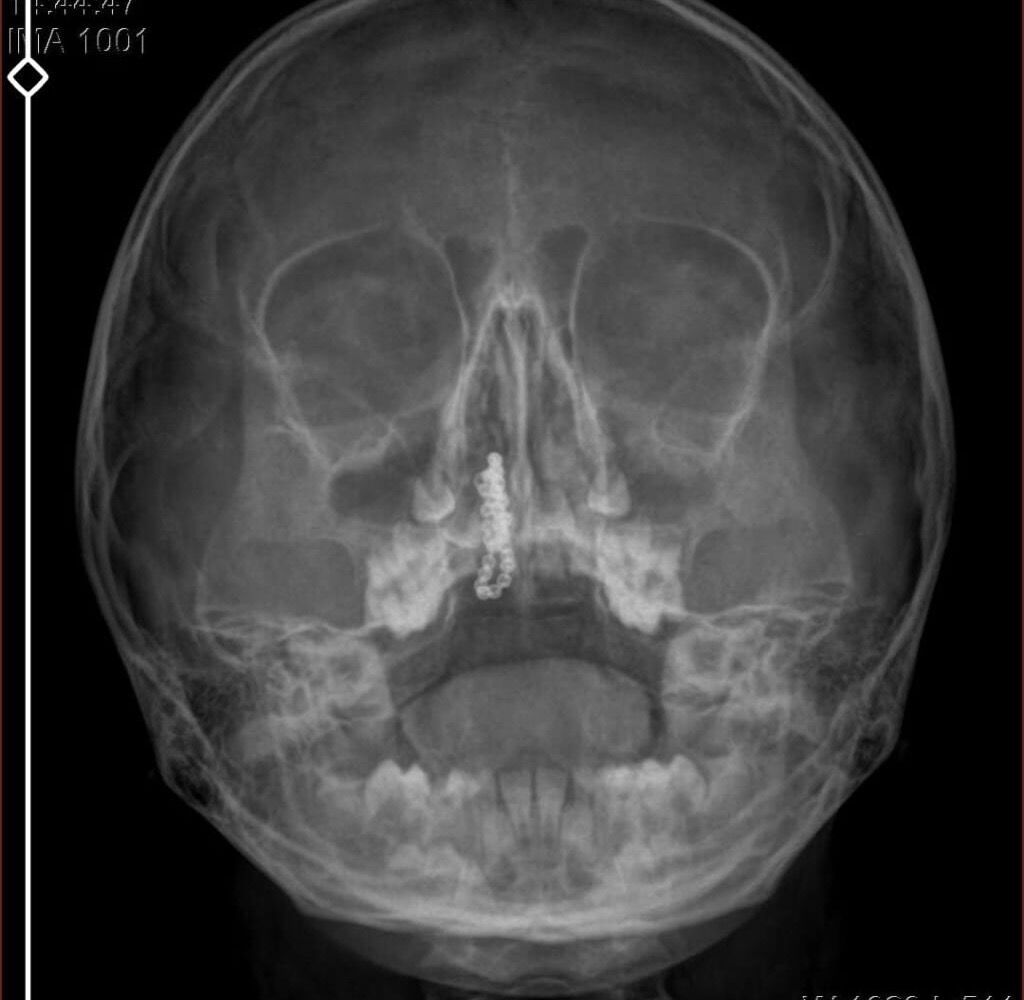

Kentte yaşayan Gökhan-Nalan Tekin çifti, yaklaşık 4 ay önce şiddetli burun kanamasının yanı sıra akıntı şikayetleriyle kızları Polen'i, bir özel hastaneye götürdü. Burada röntgeni çekilip, tetkikleri tamamlanan küçük kıza, iddiaya göre enfeksiyon teşhisi konulup, ilaç verildi. Eve dönen aile, kanama ve akıntının geçmemesi üzerine bu kez Rize Devlet Hastanesi'ne giderek Kulak Burun Boğaz Polikliniği'ne başvurdu. Devlet hastanesindeki doktorun incelemesi ve kapsamlı röntgen çekilmesi sonrası Polen'in burnunda metal cisim olduğu fark edildi. 2 yıldır burunda kaldığı değerlendirilip, küçük top şeklinde tırnak makası zinciri olduğu belirlenen cisim, başarılı ameliyatla çıkarıldı. Bir süre tedavisi sürdürülen Polen, sağlığına kavuşunca taburcu edildi. Özel hastane yetkilileri, konuyla ilgili açıklama yapmazken; aile suç duyurusunda bulunacaklarını söyledi.

Kızının burnundan sürekli siyah renkte akıntı olduğunu anlatan Gökhan Tekin, "Çocuğumun burnundan kanama ile sürekli siyah akıntı geliyordu. Özel hastaneye götürdüm. Özel hastanede film çekildi, hiçbir bulguya rastlanılmadığı söylendi. O siyah leke de enfeksiyona dayalı olan bir şey olduğu bize söylendi. Eve geldik, akıntı sürmesi üzerine bu kez devlet hastanesine başvurduk. Burunda metal zinciri fark ettiler. Böyle bir ihmalkarlık olabilir mi? Özel hastaneye gidiyoruz, paramızla rezil oluyoruz. Zincir, 2 yıldır burnunda ve devletimizin hastanesinde iyi bir doktorumuz zinciri ortaya çıkarıyor, kızım ölümden dönüyor. Ben sonuna kadar bu işin peşini bırakmayacağım. Sonuna kadar hukuk mücadelesi vereceğim. Bu da diğer hastalarımıza ibret olsun. İşte, bakın koca bir zincir. 'Bulguya rastlanılmadı' deniliyor" dedi.

Kızının ameliyat sonrası durumunun iyi olduğunu söyleyen Tekin, "İnanır mısınız bize 'Evde soba mı yanıyor? Acaba kömür isten dolayı mıdır bu?' dendi. Böyle bir şey olabilir mi? Ameliyattan çıkan parmağım kadar zincir. Devlet hastanesindeki doktor da 'Bu nasıl gözden kaçılabilir? Böyle bir pozisyon nasıl görülmeyebilir?' yorumunda bulundu. Allah'a şükür olsun atlattık. Şu anda durumu, vaziyeti iyidir. Ben şuna inanıyorum doktor da bir şans işidir. Bakın paramızla özele gideriz ya hani bizde, daha iyi ilgilenirler. Oysa devlet hastanesindeki doktorumuz olayı meydana çıkardı" diye konuştu.